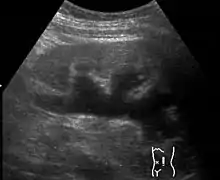

Imaging studies, such as an intravenous urogram (IVU), renal ultrasonography, CT, or MRI, are also important investigations in determining the presence and/ or cause of hydronephrosis. Whilst ultrasound allows for visualisation of the ureters and kidneys (and determine the presence of hydronephrosis and / or hydroureter), an IVU is useful for assessing the anatomical location of the obstruction. Antegrade or retrograde pyelography will show similar findings to an IVU but offer a therapeutic option as well. Real-time ultrasounds and Doppler ultrasound tests in association with vascular resistance testing helps determine how a given obstruction is effecting urinary functionality in hydronephrotic patients.[10]

Kay recommends that a neonate born with untreated in utero hydronephrosis receive a renal ultrasound within two days of birth. A renal pelvis greater than 12mm in a neonate is considered abnormal and suggests significant dilation and possible abnormalities such as obstruction or morphological abnormalities in the urinary tract.[10]